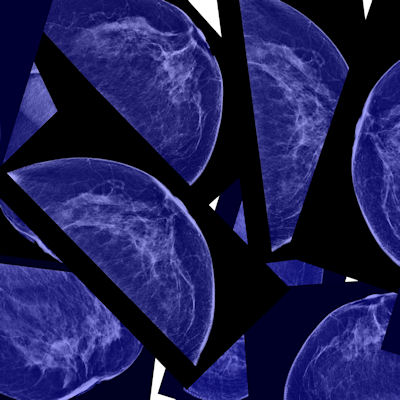

Lunit Insight MMG is one of the company's most mature radiology products. The AI software analyzes mammography images to detect suspicious lesions in mammography images, helping radiologists distinguish suspected tumor areas by providing the location of the lesion with an abnormality score reflecting the AI's confidence level, Lunit said.